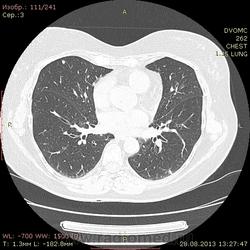

1961 г.р. В течение около 2х недель мучает сильный кашель, температура не поднималась, терапевны назначали антибиотики. Пропила неделю - без какого либо улучшения. Около полутора недель назад делали флюшку - без инфильтративных, корни немного расширены, структурны. Снгодня на флюшке появилась округлая тень слева. Решили сделать КТ - и вот результат.

Множественные мягкотканные мелкие узелки, лимфоаденопатия. Туберкалез? Саркоидоз? Mts? Не знаю чего и думать...прошу помощи.

1. Внутригрудная лимфоаденопатия. 2.Участки снижения пневматизации легочной ткани по типу "матового стекла". 3. Наличие в обоих легких узелковых образований (гранулем), преимущественно прилежащих к костальной, междолевой и межсегментарной плевре. Комплекс симптомов, наиболее характерен для Саркоидоза легких и ВГЛУ. Показано гистологическое подтверждение: трансбронхиальная внутрилегочная биопсия (информативность до 80% или медиастиноскоия и медистинотомия (информативность до 95%).

Лимфапролиферативное заболевание (ЛГМ, лимфома) vs саркоидоз. Нет тут туберкулеза.

На туберкулез легких не похоже.Лимфаденопатия. Метастазы. В меньшей степени вероятен саркоидоз.